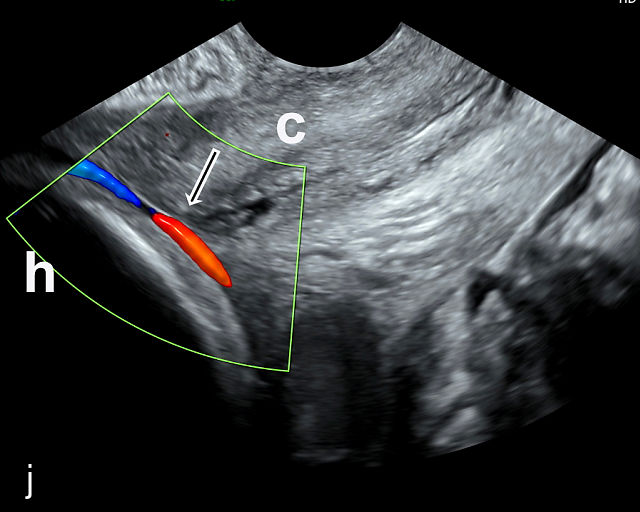

5

Placenta previa and low-lying placenta. (a) Transabdominal grayscale ultrasound image suspicious for placenta previa. The placenta (PL) appears to overlie the internal cervical os (CX). Note the time stamp: 2:19:37. (b) Transvaginal ultrasound of the same patient taken approximately 50 minutes later. Note the time stamp: 3:10:25. The internal os and the lower placental edge are both clearly seen, and the placenta does not overlie the internal os. Because the lower placental edge is 1.93 cm from the internal os, it will likely resolve by the third trimester. (c) Transabdominal grayscale ultrasound of placenta previa. The placenta (p) covers the cervix, but the cervix, especially the internal os, cannot be visualized due to shadowing. (d) Transabdominal grayscale ultrasound of placenta previa. The placenta (p) covers the cervix (c) but shadowing obscures adequate visualization. The internal os is indicated by the arrow. (e) False-positive image of placenta previa on transabdominal grayscale ultrasound. The bladder (b) is full, pushing the anterior and posterior walls of the lower uterine segment (ls) together making it appear that the placenta (p) overlies the internal os of the cervix. In reality, the line depicted by the arrowheads is where the anterior and posterior walls of the lower segment are in proximity to each other. The cervix is much lower and is obscured by shadowing (c). (f) Transabdominal grayscale ultrasound image of placenta previa. The placenta (p) covers the cervix (c), but the cervix, especially the internal os, cannot be visualized due to shadowing. b, bladder. (g) Transvaginal grayscale ultrasound image of placenta previa. The placenta (p) completely covers the internal os (arrow) of the cervix (c). The internal os can be seen clearly. h, fetal head. (h) Transvaginal grayscale ultrasound image of posterior low-lying placenta (p). The lower placental edge is clearly seen and is 1.56 cm from the internal os (arrow) of the cervix (c). The placental edge and the internal os are clearly seen. h, fetal head. (i) Transvaginal grayscale ultrasound image of a posterior placenta previa (p). The internal cervical os is clearly seen (arrow). c, cervix. (j) Transvaginal grayscale ultrasound image of an anterior placenta previa (p). The internal cervical os is clearly seen (arrow). c, cervix; h, fetal head. (k) Transvaginal grayscale ultrasound image of a posterior placenta that was thought to be low-lying on transabdominal sonography but could not be adequately assessed. This examination clearly shows the lower edge of the placenta (p) to be 2.18 cm from the internal os (arrow) of the cervix, firmly establishing that the placenta is not low-lying and allowing the patient to undergo labor safely and deliver vaginally. c, cervix. (l) Transvaginal grayscale ultrasound image of placenta previa. The placenta (p) completely covers the internal os (arrow) of the cervix (c). The internal os can be seen clearly.